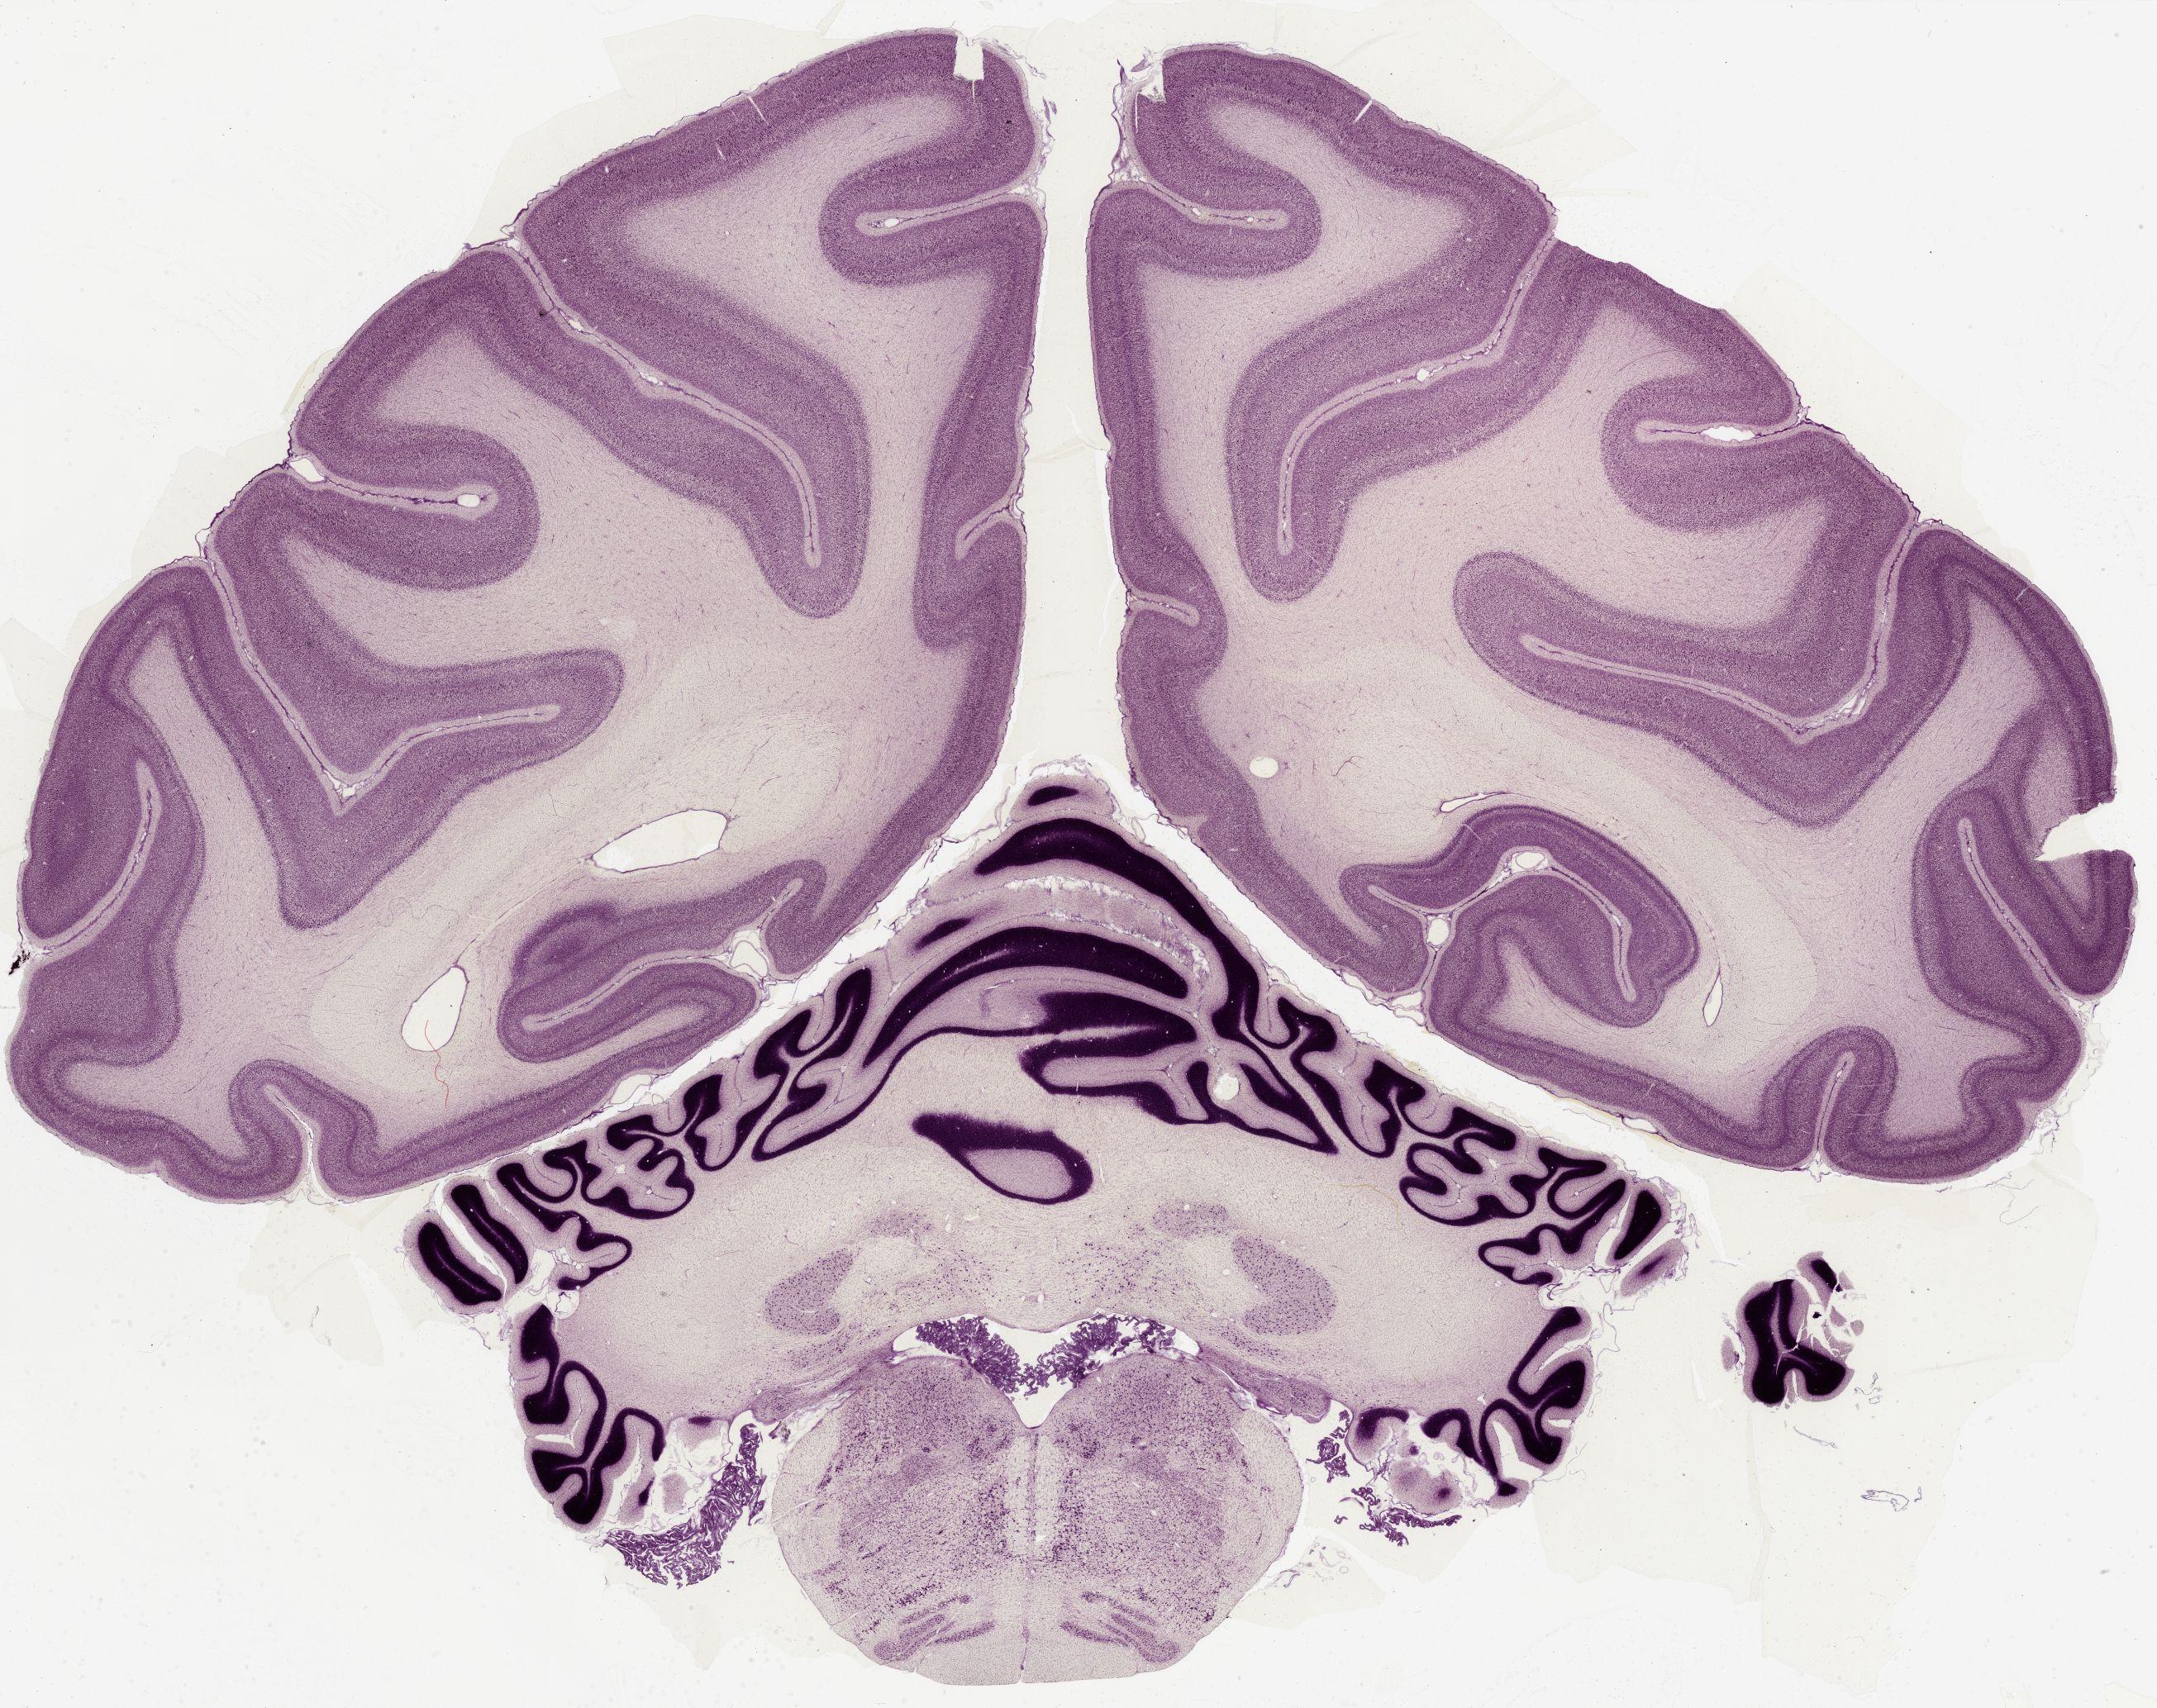

Datasets -> Macaca Mulatta -> Nissl, coronal, histo, Whole-Brain, adult

[ Metadata ]   ·   Source: Edward G. Jones

Displaying Sections 41 thru 56 of 56 Sections for this Dataset

0650 - labeled